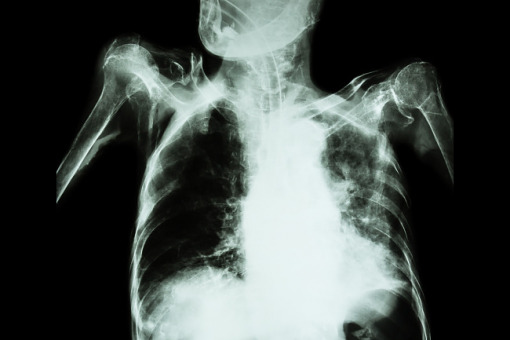

Kardiomiopatia cukrzycowa jest chorobą mięśnia sercowego związaną z przewlekłą hiperglikemią.